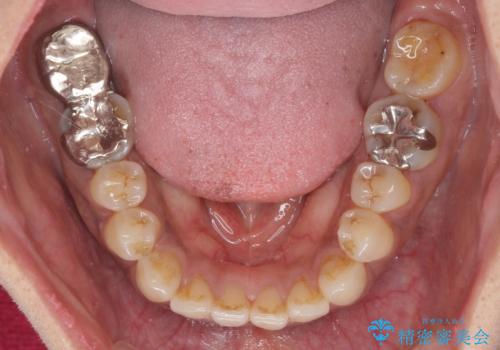

極端な上下前歯の開咬を改善 オープンバイトのインビザライン矯正

また、下顎大臼歯に根管治療が必要な歯があるため、矯正治療と並行して治療を行い、矯正後に補綴治療することとしました。

治療前に、いくらインビザライン矯正がオープンバイトを得意としているとは言え、さすがに限界があるだろうと思っておりましたが、前歯でレタスが噛めるまで改善することができました。

顔の印象も大きく変わり、患者様には大変満足していただきました。